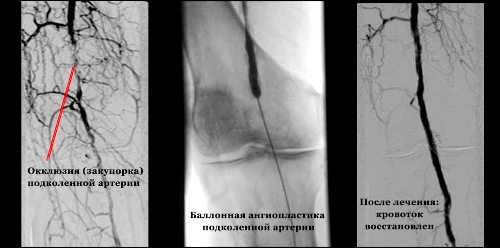

| Ангиопластика и стентирование | Расширение суженного сосуда с помощью баллона и установка стента (сетчатой трубки) для поддержания его просвета. | |

- Непрямая эмболэктомия. Она делится на два типа: ортоградная, при которой катетер вводится по направлению кровотока, и ретроградная, когда катетер вводится против него. Катетер направляется к месту эмболии для удаления тромба. В настоящее время разработан специальный катетер для эмболэктомии, который представляет собой тонкую трубку с заостренным концом и раздувающимся баллончиком на другом конце. Катетер вводится в сосуд, проходит через эмбол, затем баллончик раздувается, и катетер аккуратно извлекается вместе с эмболом.